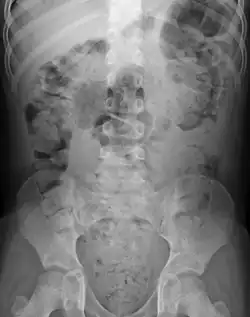

| Constipation in a young child seen on X-ray. Circles represent areas of fecal matter (stool is white surrounded by black bowel gas). | |

Abdominal X-rays are generally only performed if bowel obstruction is suspected, may reveal extensive impacted fecal matter in the colon, and may confirm or rule out other causes of similar symptoms.[26][17]